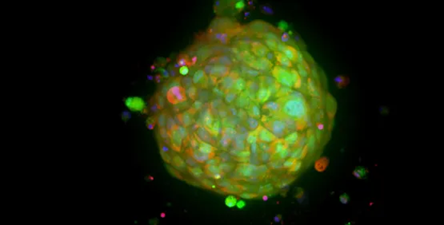

Oncology - Cancer research

Image Credit: Molecular Devices UK Ltd

Cancer researchers require tools that will allow them to more easily analyze the complex and sometimes poorly understood interactions between malignant cells and their environment, as well as discover potential treatment targets. Learn about cancer research apparatus and software, which frequently use biologically relevant 3D cellular models such as spheroids, organoids, and organ-on-a-chip systems to recreate the in vivo environment of a tumor or organ.